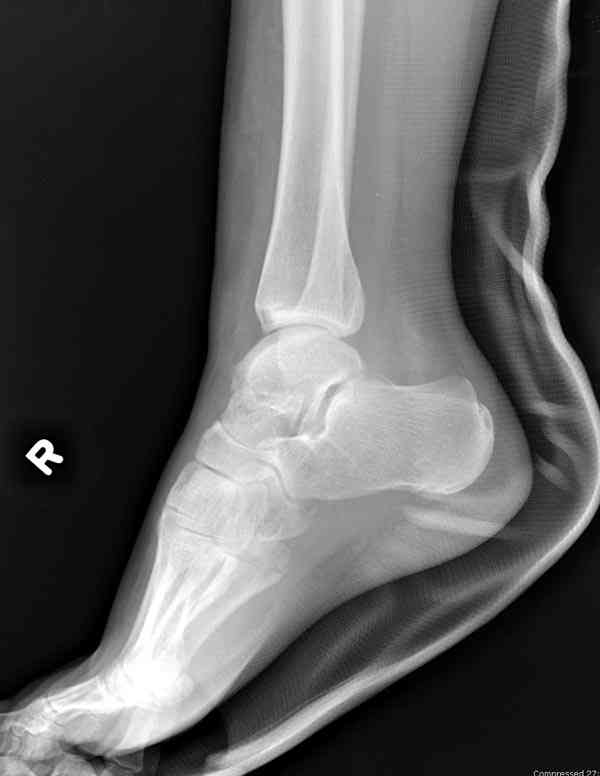

Случай с множественным оскольчатым переломом тарана оперированный из двойного доступа.

Через 2 мес.: